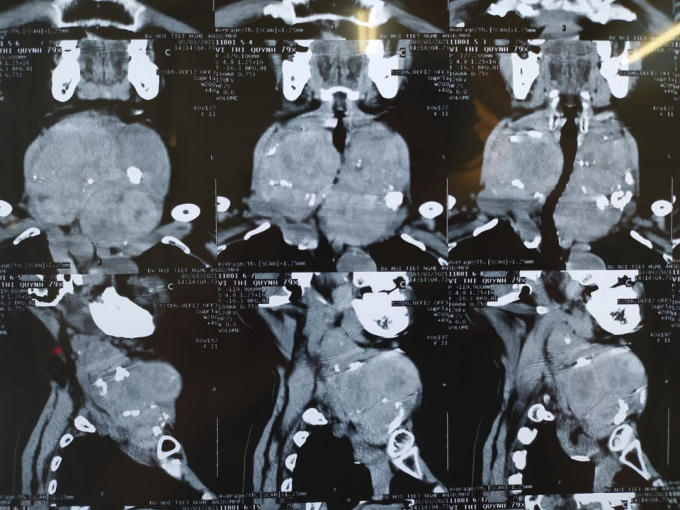

Hình ảnh cho thấy những khối u khổng lồ phát triển chèn ép khắp vùng cổ bệnh nhân.

Tại đây, qua thăm khám bác sĩ xác định hai thùy kích thước rất lớn, có nhiều khối tỷ trọng hỗn hợp, một vài khối trong có vôi hóa, các khối phát triển lan rộng ra xung quanh gây đè dây thanh và các cấu trúc lân cận, phát triển sâu xuống trung thất, vượt qua đường nối giữa hai khớp ức đòn. Cụ thể thùy phải có khối hỗn hợp âm, khối lớn kích thước 7,2 x 4,7 cm, thùy trái của bệnh nhân có nhiều khối hỗn hợp bờ đều, khối lớn kích thước 5,8 x 3,7cm. Bệnh nhâ được chỉ định mổ cắt khối u tuyến giáp.